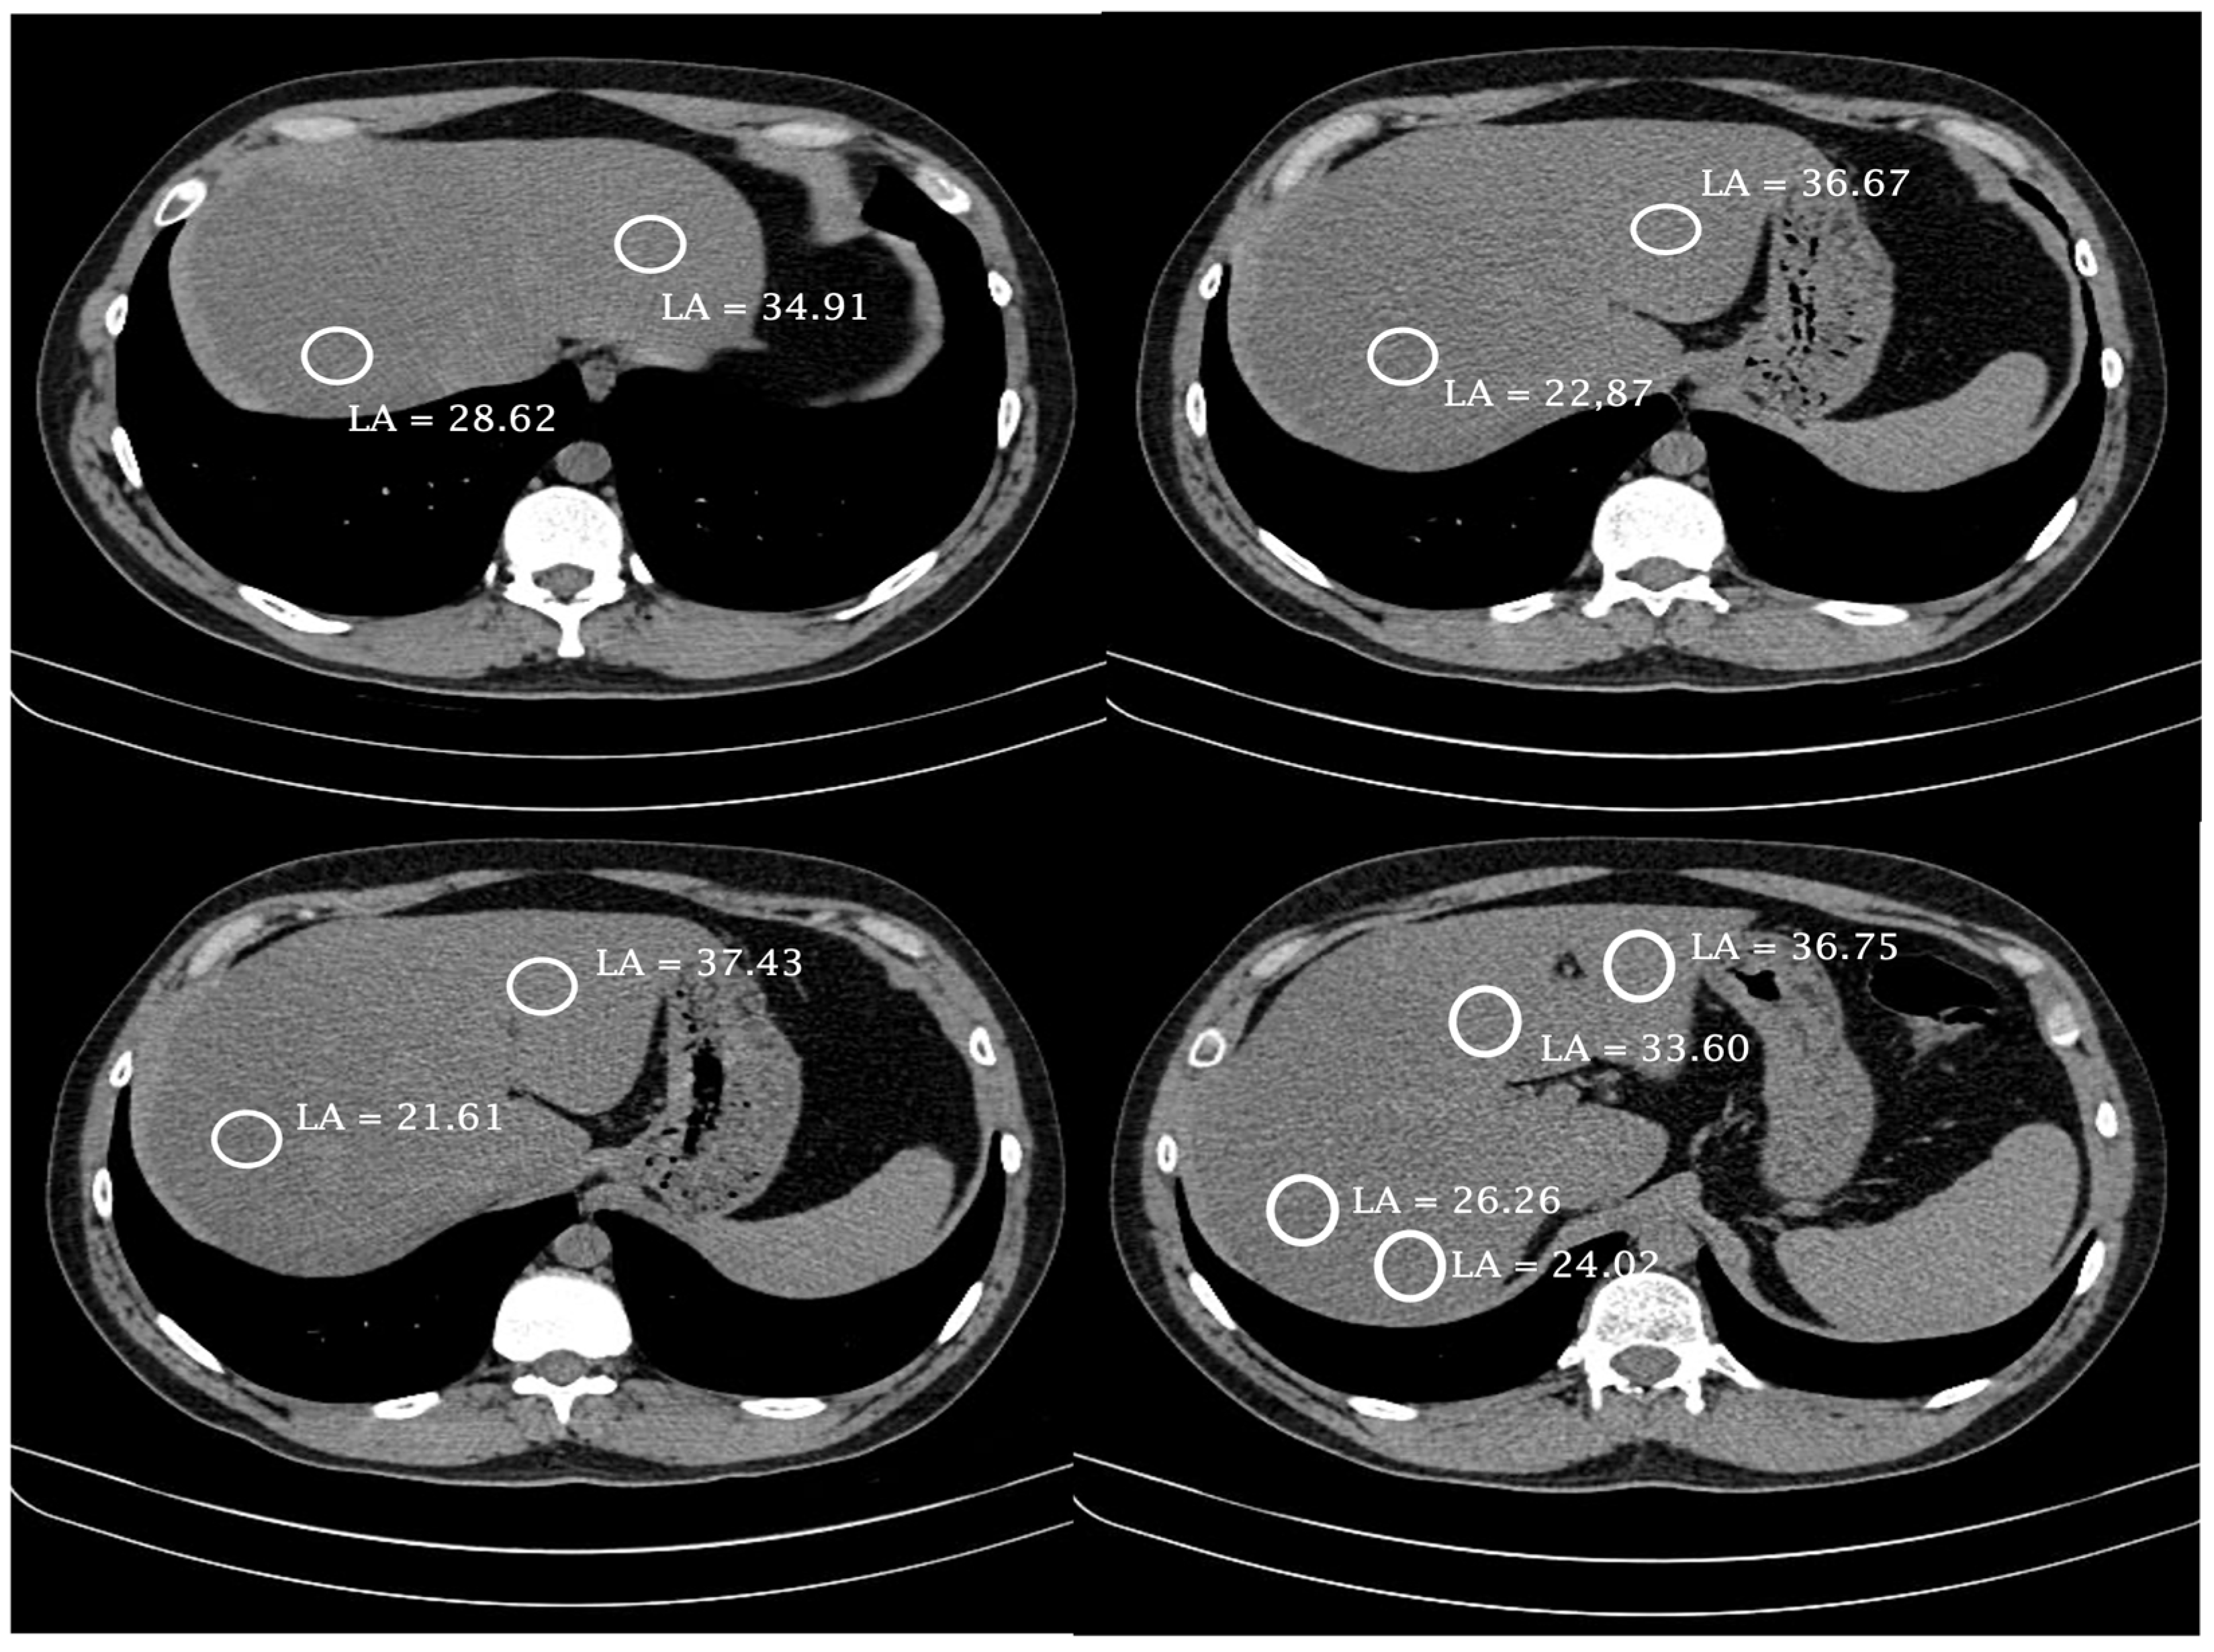

- Boyce, C.J.; Pickhardt, P.J.; Kim, D.H.; Taylor, A.J.; Winter, T.C.; Bruce, R.J.; Lindstrom, M.J.; Hinshaw, J.L. Hepatic Steatosis (Fatty Liver Disease) in Asymptomatic Adults Identified by Unenhanced Low-Dose CT. Am. J. Roentgenol. 2010, 194, 623–628. [Google Scholar] [CrossRef]

- Tahtabasi, M.; Hosbul, T.; Karaman, E.; Akin, Y.; Kilicaslan, N.; Gezer, M.; Sahiner, F. Frequency of Hepatic Steatosis and Its Association with the Pneumonia Severity Score on Chest Computed Tomography in Adult COVID-19 Patients. World J. Crit. Care Med. 2021, 10, 47. [Google Scholar] [CrossRef] [PubMed]